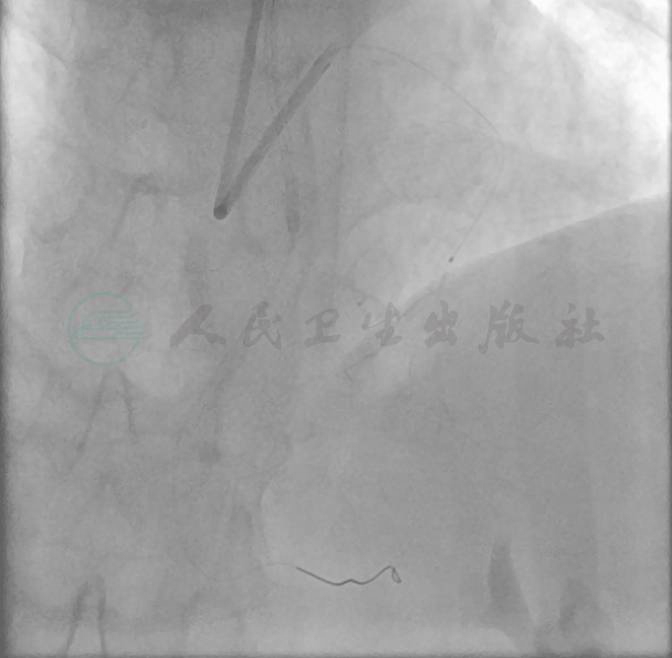

选择右侧桡动脉径路,6F 动脉鞘。造影显示:左主干未见异常,前降支中段偏心狭窄80%,回旋支中段狭窄70%,远段狭窄90%;右冠中段完全闭塞。左冠向右冠远端发出侧支循环(图1~图3)。

图2 左冠造影图(头位)